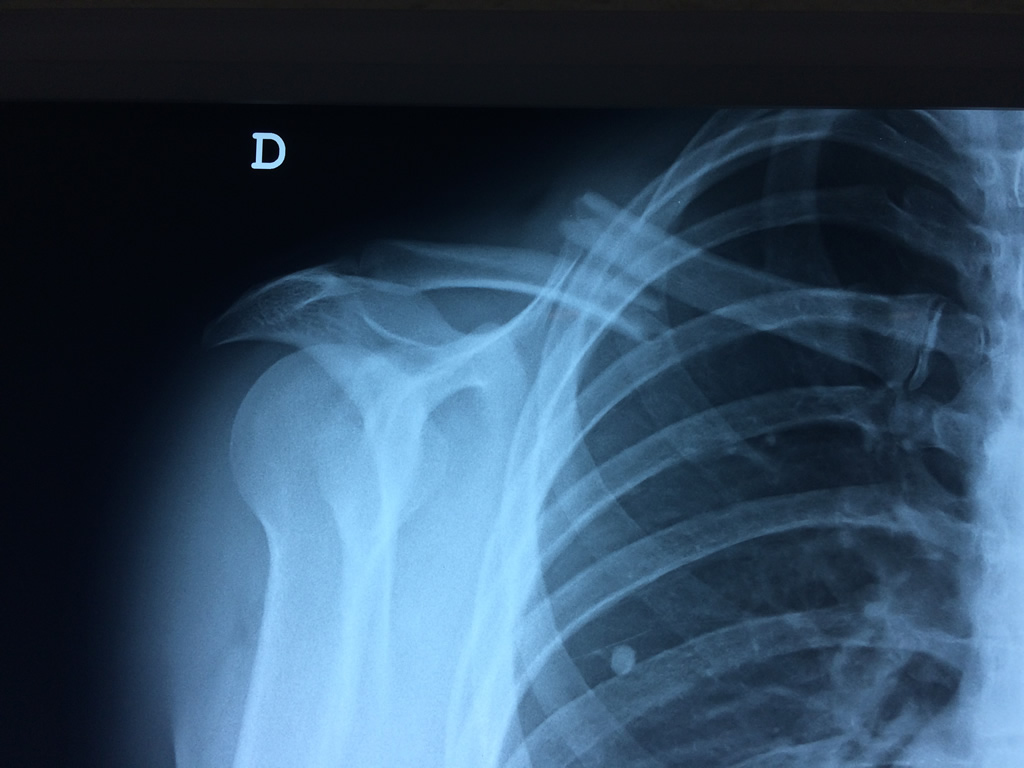

Clavícula

La clavícula es un hueso largo, con forma de "S" itálica, situado en la parte anterosuperior del tórax. Junto con la escápula forman la cintura escapular. Se puede palpar por toda su longitud y se extiende del esternón al acromion de la escápula, siguiendo una dirección oblicua lateral y posterior.

Se considera el único medio de unión entre el miembro superior y el tórax. A pesar de su aspecto, similar al de un hueso largo, posee una estructura semejante a la de un hueso plano, ya que carece de epífisis y de diáfisis, lo que la harían entrar dentro de la clasificación de hueso largo. Carece de un canal medular propiamente dicho.